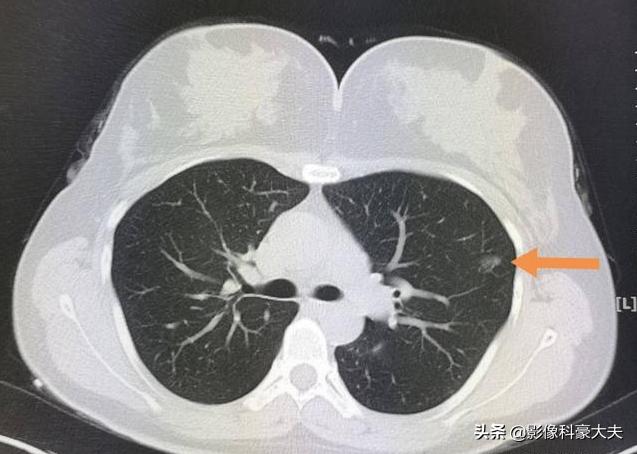

像这个病灶贴近胸膜,是浸润性肺腺癌,低分化,通过胸腔镜微创手术切除,五六天就可以出院。因为肿瘤已经侵犯胸膜,分化也不好,术后做了预防性化疗,5年多没有复发,提示治愈。